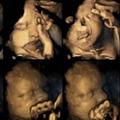

Maternica Fotografije nerojenih otrok kadilk Avtorica raziskave Nadja Reissland si želi, da bo z raziskavo prepričala bodoče matere, da prenehajo s kajenjem